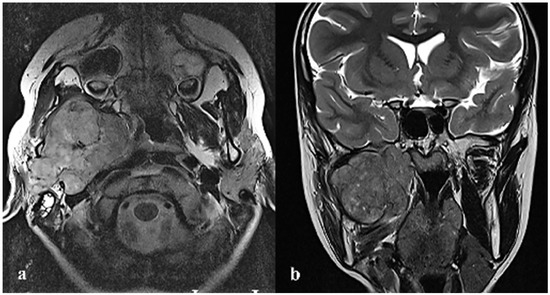

2. Case Report